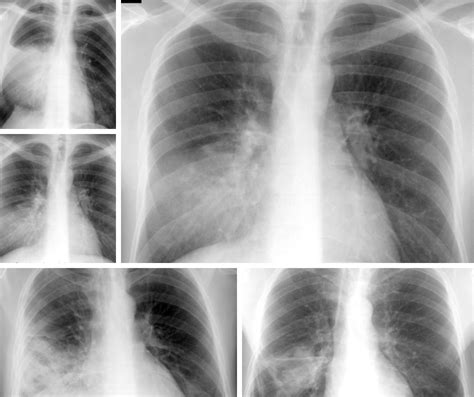

Prezentăm cazul unui pacient, de sex masculin, în vârstă de 2 ani și 6 luni, internat în clinica noastră pentru hiperpirexie, tuse productivă, rinoree și inapetență. Examenul clinic la internare a pus în evidență stare generală influențată, facies palid, suferind, febră, tuse productivă, rinoree, murmur vezicular diminuat pe partea dreaptă, saturație în oxigen 97%, și inapetență. Analizele de laborator au relevat leucocitoză marcată cu neutrofilie, anemie și markeri inflamatori intens crescuți.

Radiografia toracică a pus în evidență un focar congestiv la nivelul lobului inferior drept. Hemocultura a fost negativă. S-a inițiat tratament simptomatic și antibiotic (Ceftriaxonă), dar datorită evoluției nefavorabile, radiografia de control a arătat o zonă de condensare bazal drept, asociind o colecție pleurală închistată bazal și laterotoracic drept.

S-a efectuat și computer tomografie (CT) toracică, evidențiindu-se un proces pneumonic bisegmentar în lobul inferior drept, cu câteva pneumatocele grupate subpleural, asociind în ambii plămâni arii de hiperinflație lobulară. Astfel, s-a ridicat suspiciunea unei pneumonii verosimil stafilococice, motiv pentru care s-a asociat Vancomicină intravenos, cu evoluție favorabilă.